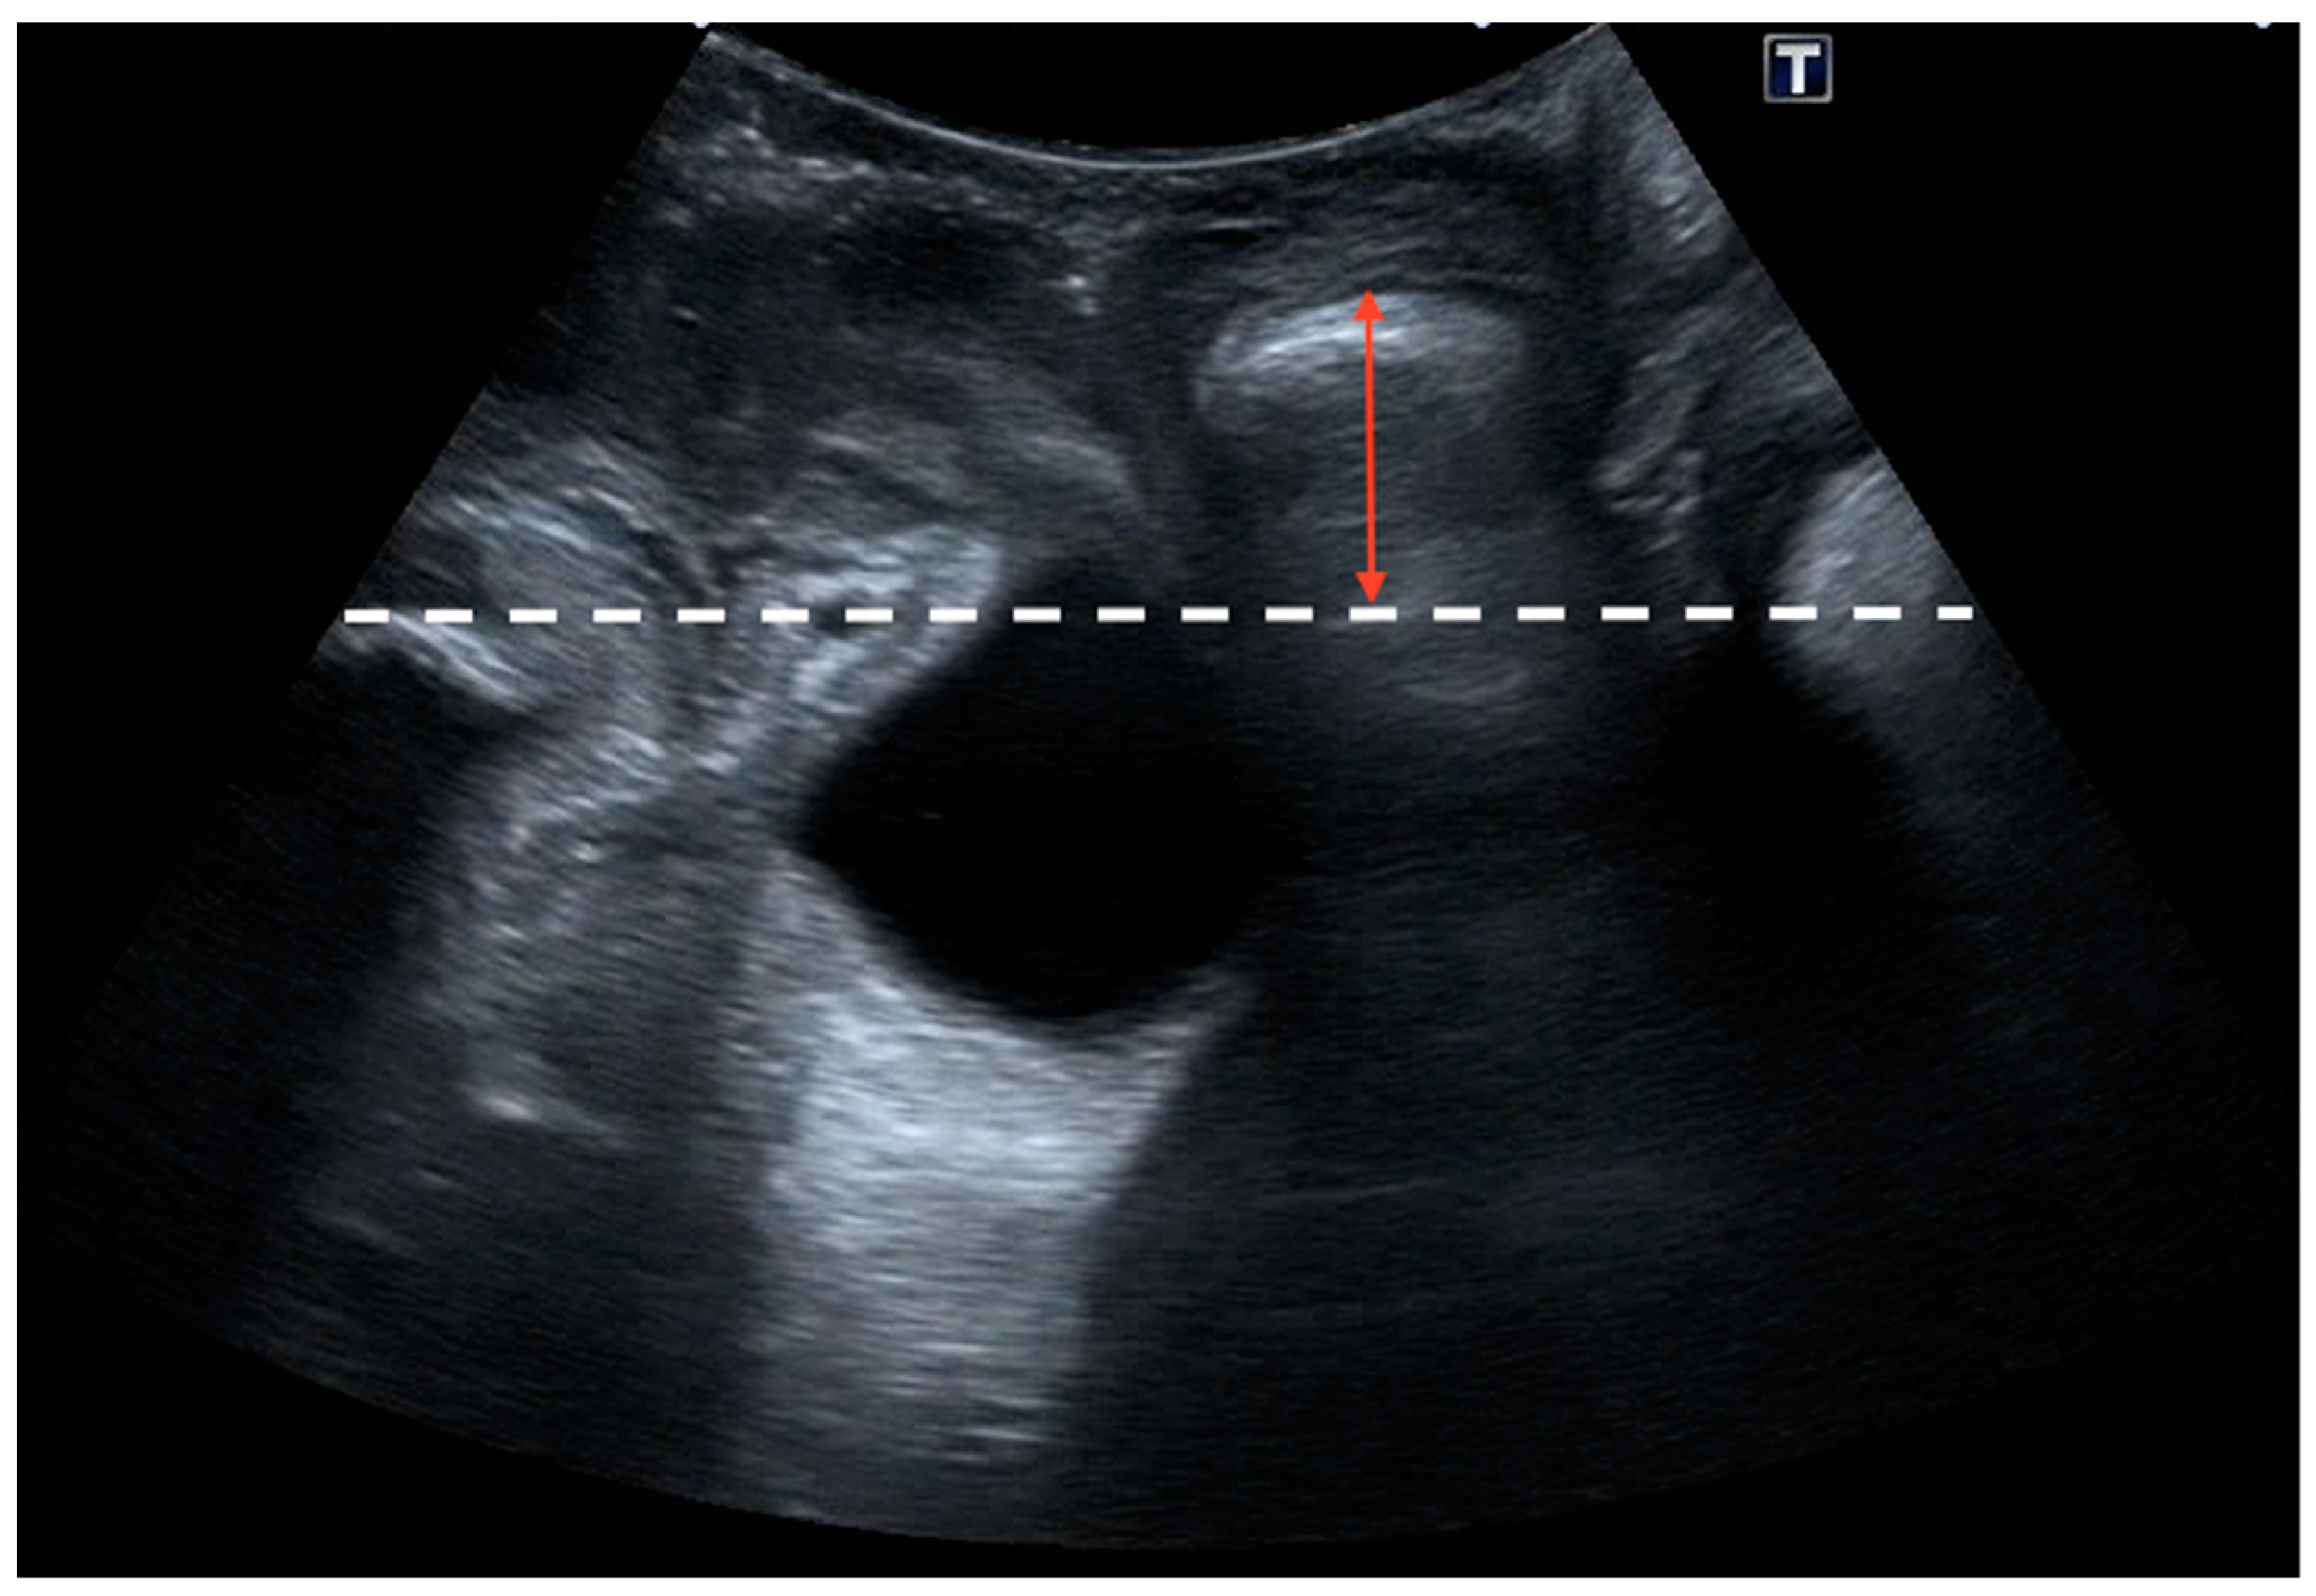

2.2. Ultrasound Examination